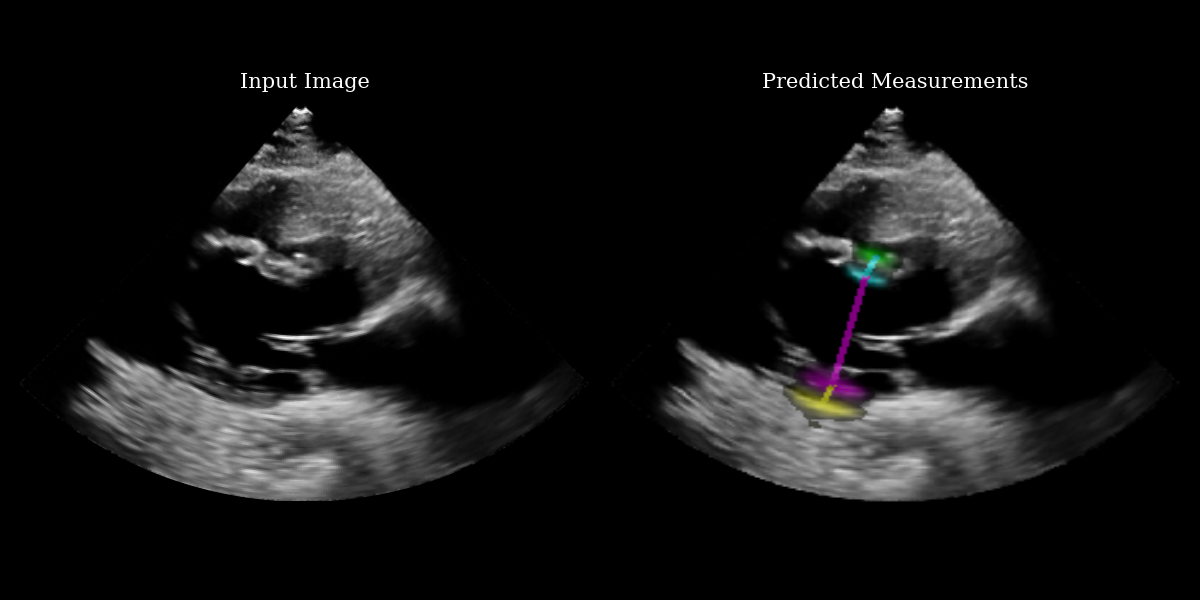

# use visualization function to visualize heatmaps and measurement lines on the input image

images_with_measurements = model.visualize_logits(batch, logits)

# Plotting

fig, (ax1, ax2) = plt.subplots(1, 2, figsize=(12, 6))

# Plot input image

ax1.imshow(img_np, cmap="gray")

ax1.set_title("Input Image", fontsize=15)

ax1.axis("off")

# Plot output with measurements

ax2.imshow(images_with_measurements[0])

ax2.set_title("Predicted Measurements", fontsize=15)

ax2.axis("off")

EchoNetLVH Example Output

The EchoNetLVH model ouptuts 4 heatmaps – one for each key point. The heatmaps indicate the probability that each pixel contains the key point. Because of this, we need a function to extract the key point from a given heatmap. There are various ways to do this – we implement a center-of-mass approach, preserving differentiability.

What we print below is the set of key points represented as indices with respect to the input image matrix.

Measurement type: [H1, W1] -> [H2, W2]

LVPW: [299 217] -> [287 226]

LVID: [287 226] -> [182 286]

IVS: [182 286] -> [187 281]